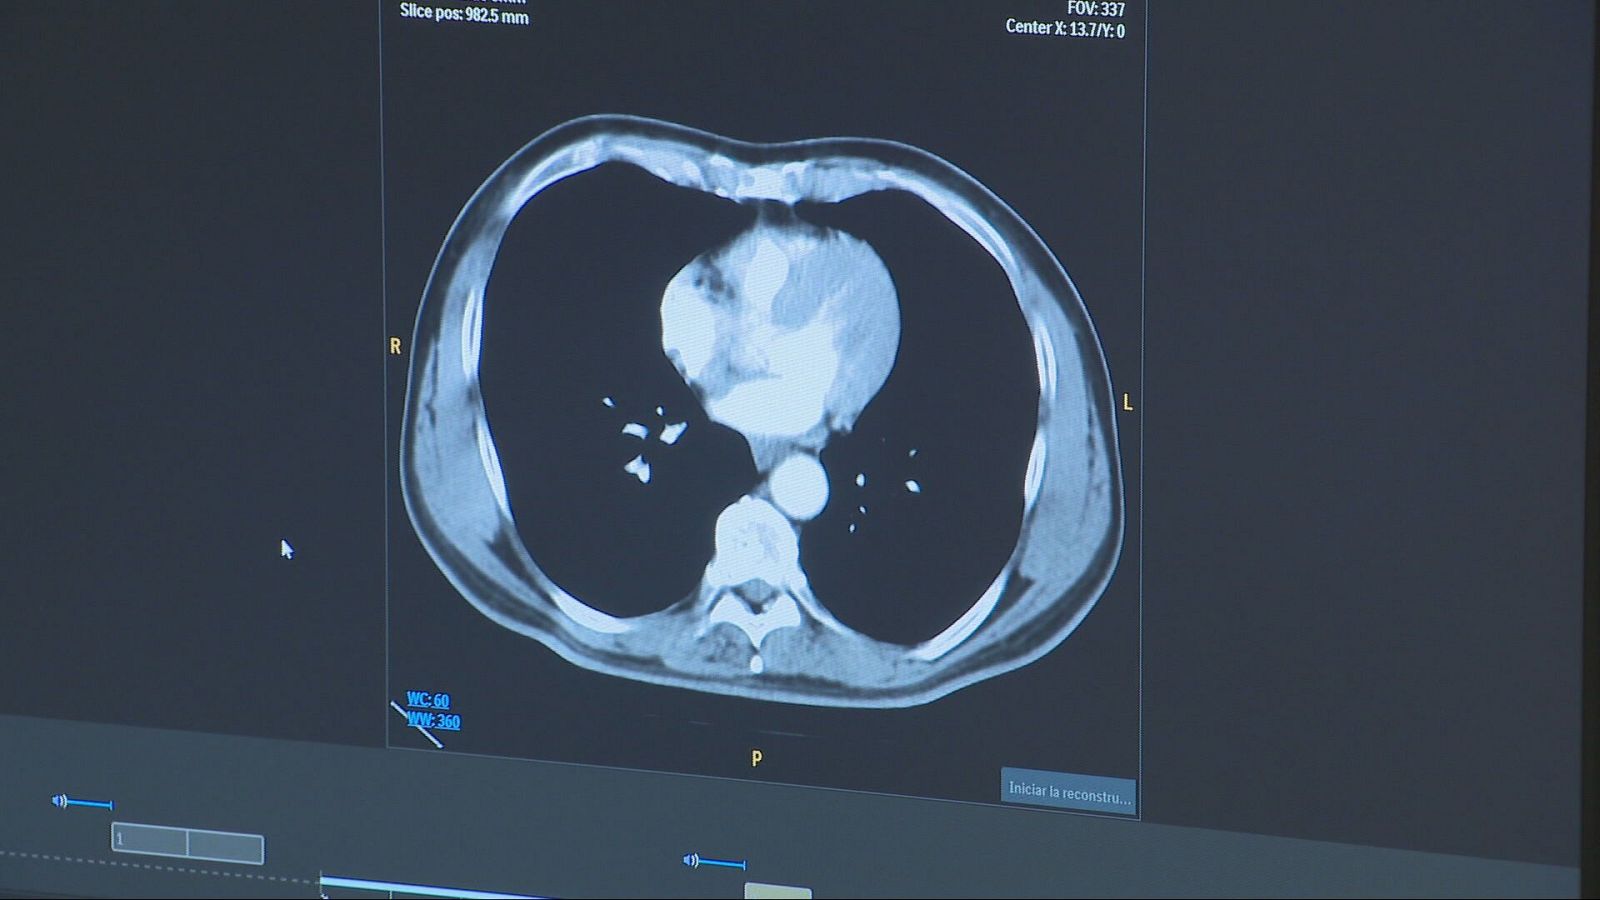

Una tècnica pionera millora la supervivència dels pacients amb càncer de pulmó

7.000 professionals d'arreu del món participen fins dimarts en el congrés més important del món sobre càncer de pulmó, el més mortífer i el segon en...